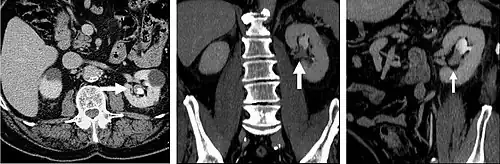

FIGURE 8. Selected images from a CT Urography protocol CT. 8a is an axial CT image from the renal parenchymal phase. There is a mildly enhancing soft tissue mass in the left renal pelvis (arrow) consistent with a transitional cell carcinoma. Figure 8b (coronal reformats) and 8c (left oblique coronal reformats) demonstrate the double bolus technique of CT Urography. These images confirm soft tissue mass (arrows) in the renal pelvis with contrast excretion into the collecting system (arrowheads).